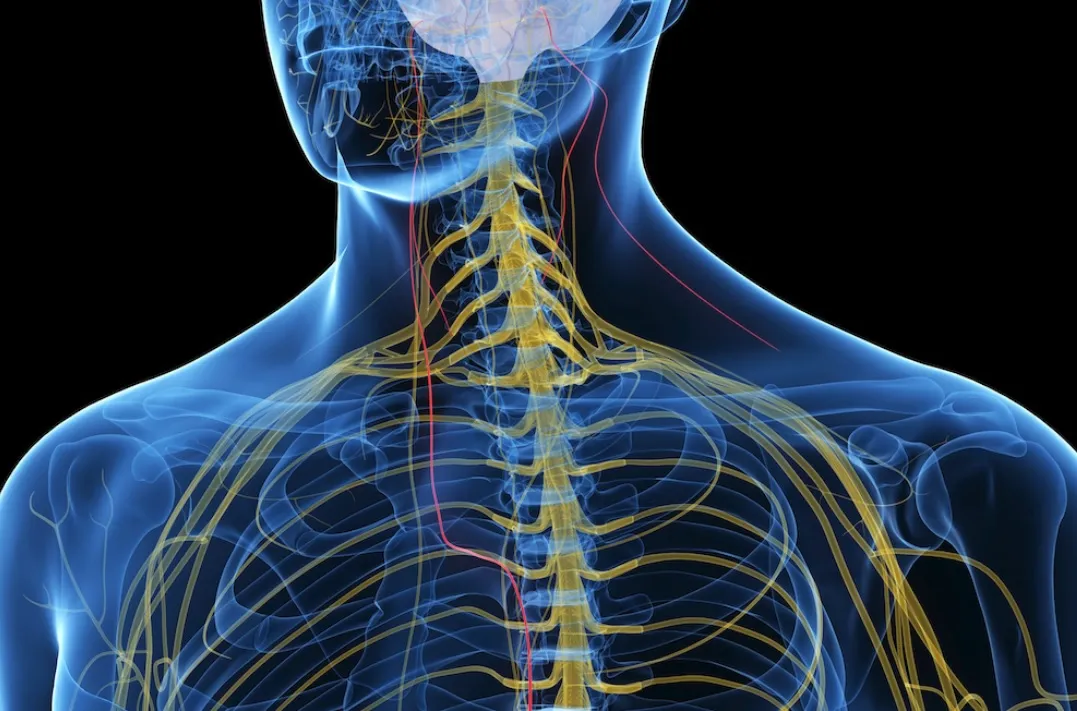

Институт медицинских исследований им. Файнштейна (США) обнаружил интересную взаимосвязь между воспалительными заболеваниями и специфическими рецепторами блуждающего нерва. Хорошо известно, что мозг посылает сигналы для контроля воспалительной реакции, однако иногда «тормоза отказывают» и у человека возникает хроническое воспаление, вызывающее ревматоидный артрит или рассеянный склероз.

Эти результаты доказывают, что специфические рецепторы в блуждающем нерве не только обнаруживают воспаление, но и контролируют его, сигнализируя в мозг, когда необходимо отключить воспалительную реакцию. Открытие этого факта позволит создать новые методы лечения для людей с хроническим воспалением, которое вызывает различные заболевания, например при помощи стимуляции блуждающего нерва.